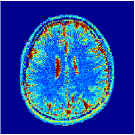

VI-E In-vivo experiments

Two sets of experiments were conducted here: first, we used the 2D and 3D acquisition sequences for scanning a healthy volunteer’s brain (real-world acquisitions). Figures 6 and 7 display the parametric maps reconstructed from 2D spiral and radial readouts. We computed the T1, T2 and proton density (PD) maps using baseline reconstruction algorithms ZF, VS, LR, FLOR, AIR-MRF and our proposed LRTV. While baselines use DM either for quantitative inference or also during reconstruction (i.e. AIR-MRF), we further compare the DM-free LRTV’s performance when cascaded to DM, KM and MRFResnet for quantitative inference. For the 3D spiral acquisitions we compared LRTV and its closest competitor VS in Figure 8. Outcomes from other tested algorithm are displayed in the supplementary materials (Figure S5). Since FLOR does not use dimensionality-reduction, our system ran out of memory during 3D reconstruction; hence results are not reported in this case.

VI-E1 Discussion

The LRTV-DM and LRTV-MRFResnet perform on par, and both outperform all tested baselines for reconstructing T1, T2 and PD maps in all acquisition schemes. This can be observed both visually in Figures 6, 7, 8, S2 and S3, and quantitatively in Table IV across all tested metrics. Other baselines were unable to successfully remove the under-sampling artefacts in TSMIs, and these errors propagated to the parameter inference phase and resulted in inaccurate maps. Temporal-only priors incorporated within LR are shown insufficient to regularise the inverse problem and LR sometimes (e.g. 2D spiral acquisitions) can admit solutions with even stronger artefacts than the model-free ZF baseline. This issue was previously studied for other non-Cartesian MRF readouts that similar to our spiral/radial trajectories, miss to sample the corners of the k-space in all timeframes (see section 2.2.2 and figure 2 in [19]). In the absence of reference for the k-space corners information, the LR iterations despite minimising the objective can converge to solutions with high-frequency artefacts, as visible in the computed maps. This highlights the need for adding an appropriate spatial-domain regularisation. FLOR reduces the LR’s artefacts but this improvement is limited because the suggested nuclear norm penalty does not incorporate an explicit spatial regularisation. Further for reducing artefacts, FLOR can introduce an undesirable bias in the computed T1/T2 maps e.g. see error maps in Figures S2 and S3. The non model-based VS baseline incorporates spatial regularisation and results in spatially smoother maps than ZF and LR, but it is unable to output artefact-free images. Further and consistent with our in-vitro experiment, we observe that VS overestimates the T2 values (e.g. in White and Grey matter regions) in tested 2D acquisitions i.e. the spatial regularisation trades off agains the quantification accuracy. The model-based AIR-MRF adds spatial regularisation through 2D/3D low-pass Gaussian filters however this trades off the sharpness of the computed maps and can increase the errors at the tissue boundaries (we searched Gaussian spreads that keep the blurs and high-frequency artefacts minimal). For our acquisition readouts, Gaussian filters performed better than disk filters of [19] for avoiding strong Gibbs artefacts. On the other hand, the spatiotemporally regularised LRTV greatly improves the TSMI reconstructions i.e. 4 dB enhancement compared to the closest competitor baseline (Table IV). This enables computing accurate and aliased-free multi-parametric inference using DM or the DM-free learning-based alternative MRFResnet as visible in Figures 6, 7, 8, S2 and S3. MRResnet and DM score competitive quantitative inference results i.e. T1 and T2 MAPE less than 5% and 9%, respectively (Table IV). KM also outputs comparably accurate T1 maps, however this shallow learning model despite having a model size larger than MRFResnet, is unable to learn accurate T2/PD quantification and it results in poor estimated maps, consistent with our observations in section VI-C.